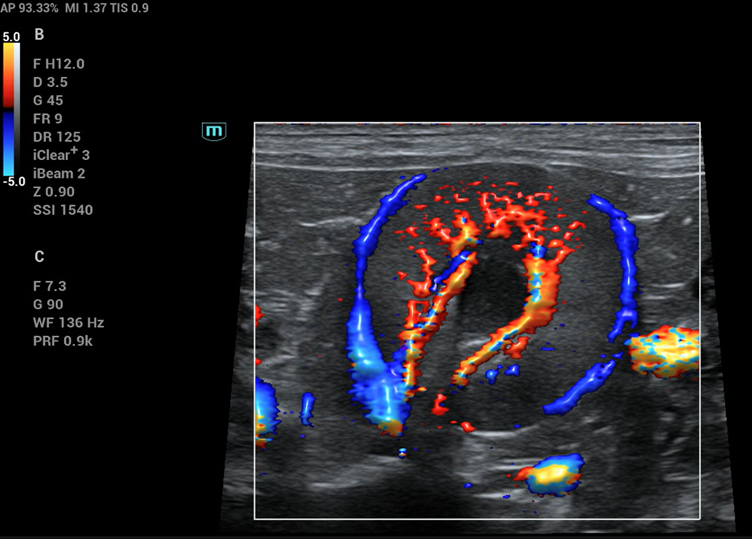

Colour flow doppler in a canine kidney from Mindray Vetus 80

This is what most people think of when you say Doppler and is generally just called Colour Doppler (CF) though can also be referred to as Colour Flow Doppler (CFD) and/or Colour Doppler Imaging (CDI). It is displayed as a colour overlay in a window over a B-mode (or M-mode) image. It is not specific for blood flow, though visualising blood flow is the most common use and detects motion relative to the transducer.

When scanning the abdomen of a panting or otherwise wriggling patient, you will notice colour filling the window (known as flash artefact). This is caused by the motion of the tissues relative to the transducer. Colour Doppler can appear very sensitive to different velocities based on how the settings are adjusted, and there are various artefacts that can impede interpretation if not set correctly. It also has a maximum velocity that can be displayed (Nyquist limit) before artefacts are seen.

As shown in the image, the two colours will appear in the direction of motion relative to the probe. The standard setup is; blue away from the probe, red towards the probe and green, in cardiac imaging, which reflects the degree of flow disturbance present.

Colour Doppler is used widely in small animal and equine practice and becoming increasingly important in farm animal practice.